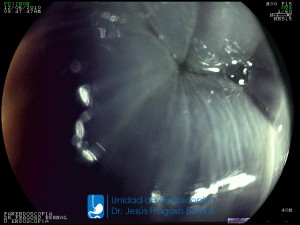

La Unidad de Endoscopía fue creada en 2002 por el Dr. Jesús Fragoso Bernal, es pionera en el estado por la utilización de la tecnología más avanzada, que nos permite ofrecer servicios integrales de diagnóstico y tratamiento para las enfermedades del aparato digestivo.

"La Unidad de Endoscopía se ha caracterizado por un progreso continuo desde su inicio marcando la pauta en los procedimientos endoscópicos en el estado de Tlaxcala y estando siempre a la vanguardia tecnológica."